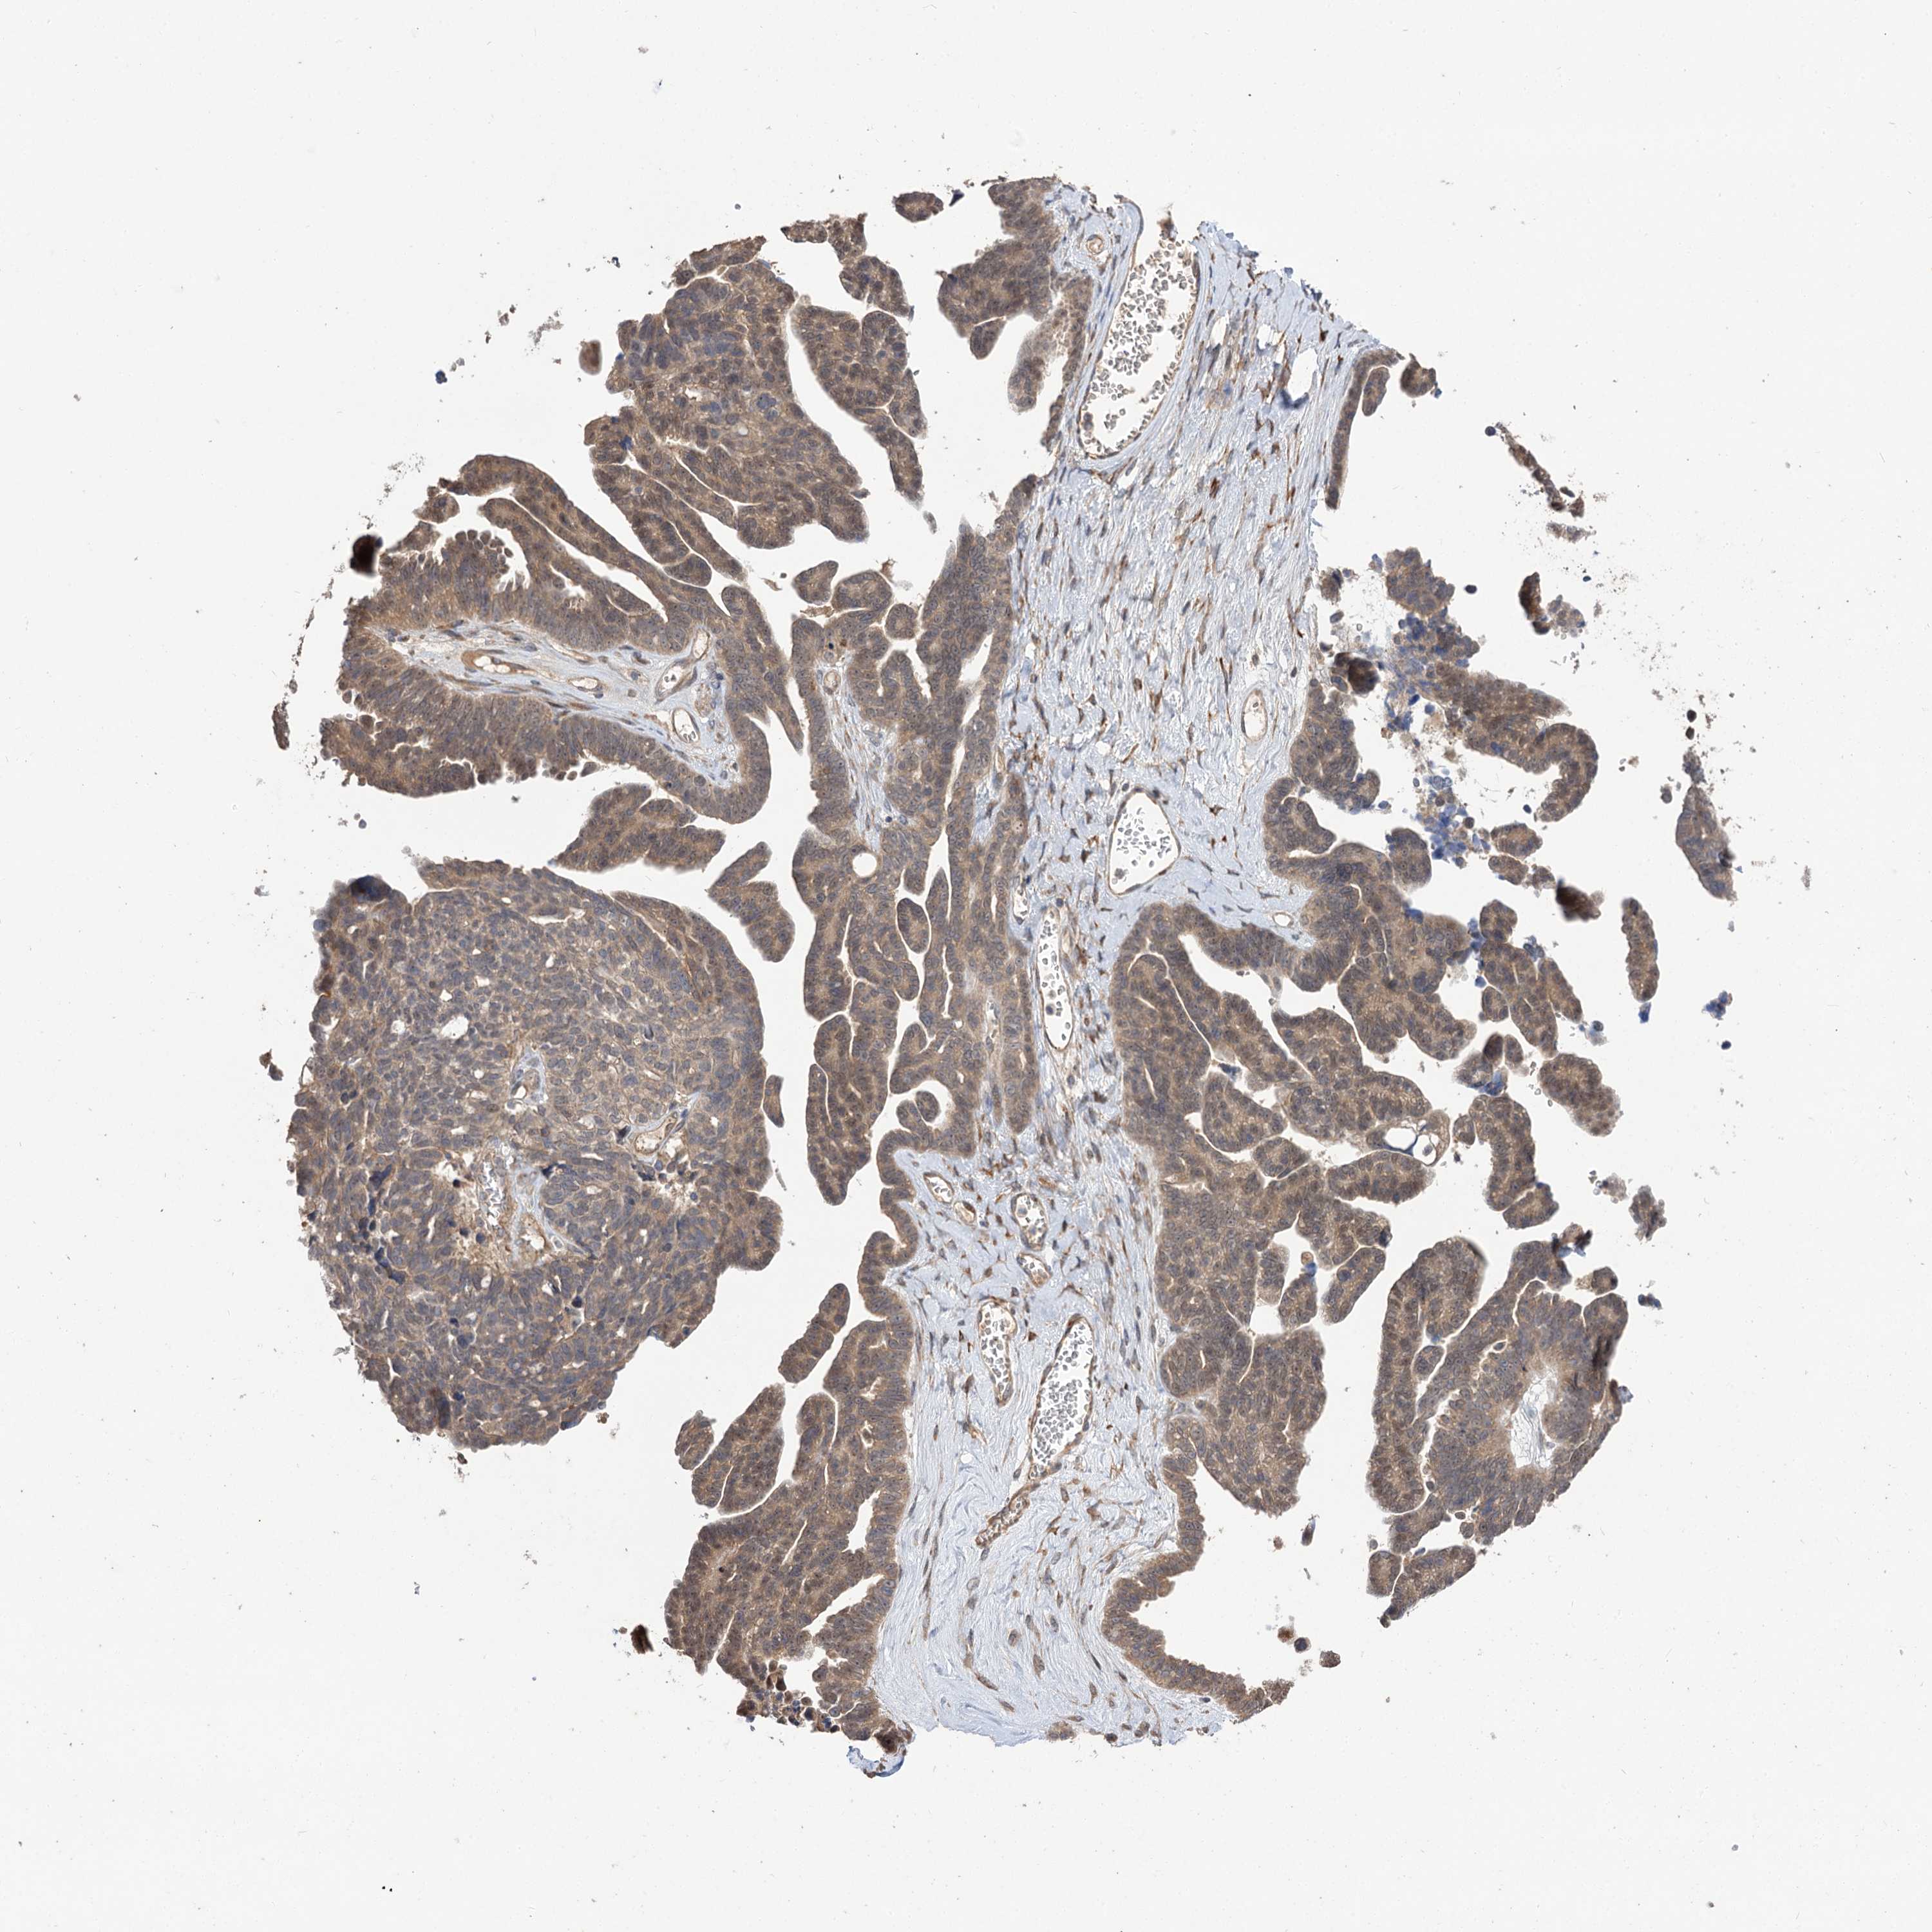

OVARIAN CANCER - Protein expressioni

A mouse-over function shows sample information and annotation data. Click on an image to view it in a full screen mode. Samples can be filtered based on level of antibody staining by selecting one or several of the following categories: high, medium, low and not detected. The assay and annotation is described here.

Note that samples used for immunohistochemistry by the Human Protein Atlas do not correspond to samples in the TCGA dataset.

Antibody stainingi

Antibody staining in the annotated cell types in the current human tissue is reported as not detected, low, medium, or high, based on conventional immunohistochemistry profiling in selected tissues. This score is based on the combination of the staining intensity and fraction of stained cells.

Each image is clickable and will lead to virtual microscopy that enables deeper exploration of all samples and also displays staining intensity scores, fraction scores and subcellular localization as well as patient and tissue information for each sample.

Antibody HPA038850

Antibody HPA038851

Cystadenocarcinoma, serous, NOS

Carcinoma, endometroid

Cystadenocarcinoma, mucinous, NOS

Carcinoma, NOS